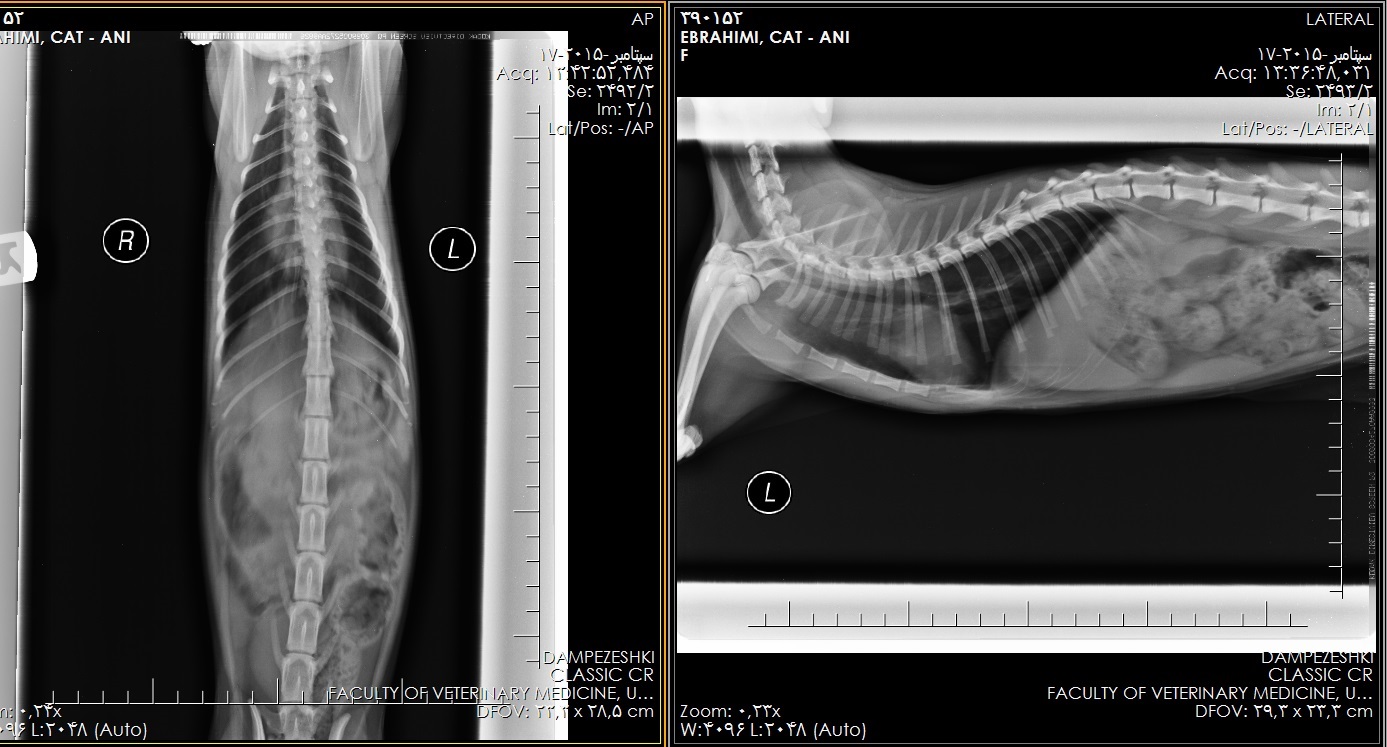

باعرض سلام و خسته نباشید.گربه 5.5 ماهه ای دارم که هنگام بازی کردن و دویدن به نفس نفس می افته و بعضی وقتها هم صدای عجیبی از خودش درمیاره و یا هنگام خواب هم صدایی شبیه غر غر کردن از خودش درمیاره.البته نمی دونم این صداها طبیعیه یا می توه مربوط به بیماریش باشه.وقتی برای زدن واکسن به دامپزشکی مراجعه کرده بودم هنگام معاینه دامپزشک فرمودن که ریه های گربه م کمی حساس شده ولی دارویی تجویز نکردن و توصیه کردن از دود سیگار دور نگهش دارم و گفتن یه عکس از ریه برای تشخیص بهتر گرفته بشه.میخواستم نظر شما رو در مورد عکس و گزارش رادیولوژی که ضمیمه کردم بدونم و توصیه ها و یا درمان خاصی اگر لازم هست لطفا بفرمایید.( این سوال 10 سال قبل مطرح شد و 10 سال قبل به این سوال پاسخ داده شده است. )